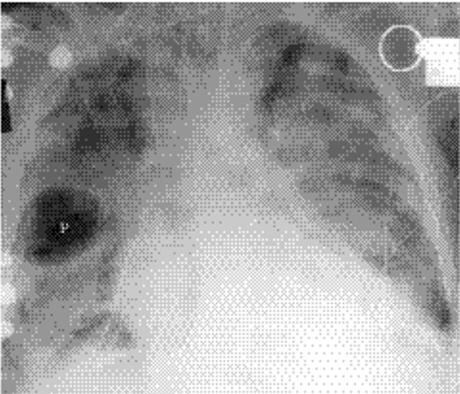

Figure 5.3 Silhouette sign of middle lobe pneumonia. A. Posteroanterior chest radiograph: loss of visualization of right heart border. B.Lateral chest radiograph: corresponding middle lobe pneumonia (P).

Lung opacity contacting a mediastinal or diaphragmatic border will obliterate or silhouette that border (“silhouette sign”). Right middle lobe opacity can be subtle on the frontal CXR, necessitating careful scrutiny of the right heart border (Fig. 5.3). Lingular disease obliterates the left heart border (Fig. 5.4), whereas lower lobe opacity may obscure a hemidiaphragm.